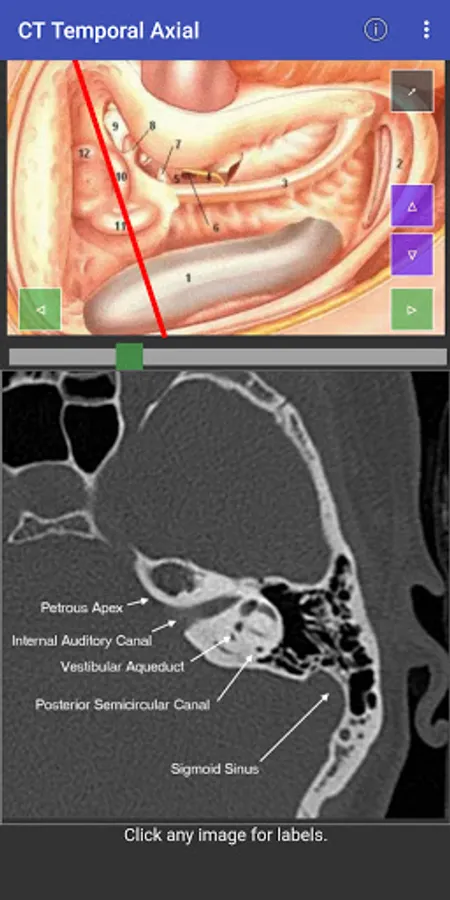

For easy of understanding CT scan anatomy, the content is correlated in two planes, with one serving as a reference. Hence it is much easier to understand the anatomy as we face in the clinical situation. Both the planes can be individually scrolled, so depth is easier to understand.